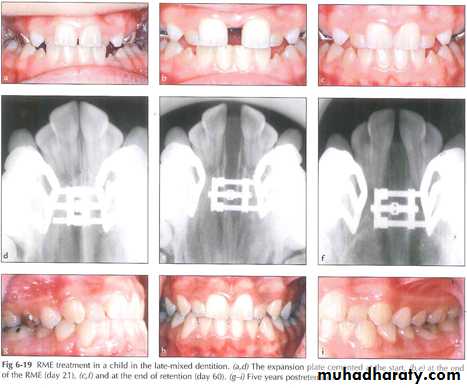

RMT Treatment in Posterior Skeletal Crossbite

There are two types of posterior crossbite: the dentoalveolar crossbite (palatally inclined maxillary teeth) and the skeletal crossbite ( narrower dimension in the maxilla than mandible). In the skeletal crossbite tipping of the premolars and molars may result in bone dehiscence and and gingival recession ;therefore ,rapid maxillary expansion (RME) .An activation force above the recommended value (1-1.5 mm) per activation will result into overrotation of the mesiobuccal root, which may cause marginal recession which can be exposed many years after treatment has been completed and generally required a soft tissue graft for root coverage. The primary indications for root coverage procedures are esthetic demands, root hypersensitivity, and management of shallow root caries lesions and cervical abrasions.